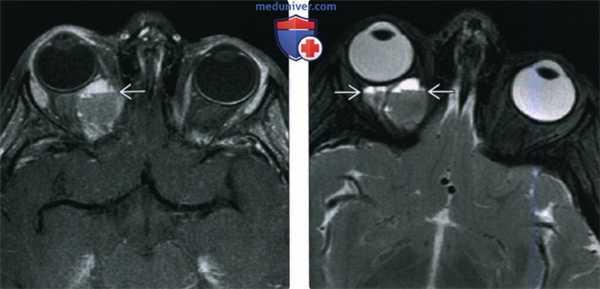

(Слева) При аксиальной Т1ВИ С+ FS у ребенка старшего возраста с обострением хронического правостороннего проптоза, обусловленного геморрагической лимфатической мальформацией глазницы, определяется жидкость белковою и геморрагического характера; видны уровни «жидкость-жидкость» на границе раздела сред.

(Справа) При аксиальной MPT Т2 FS у этого же пациента за глазным яблоком визуализируется крупное объемное образование с характерными уровнями «жидкость-жидкость». Различная высота уровней позволяет сделать заключение о многокамерном объемном образовании глазницы.